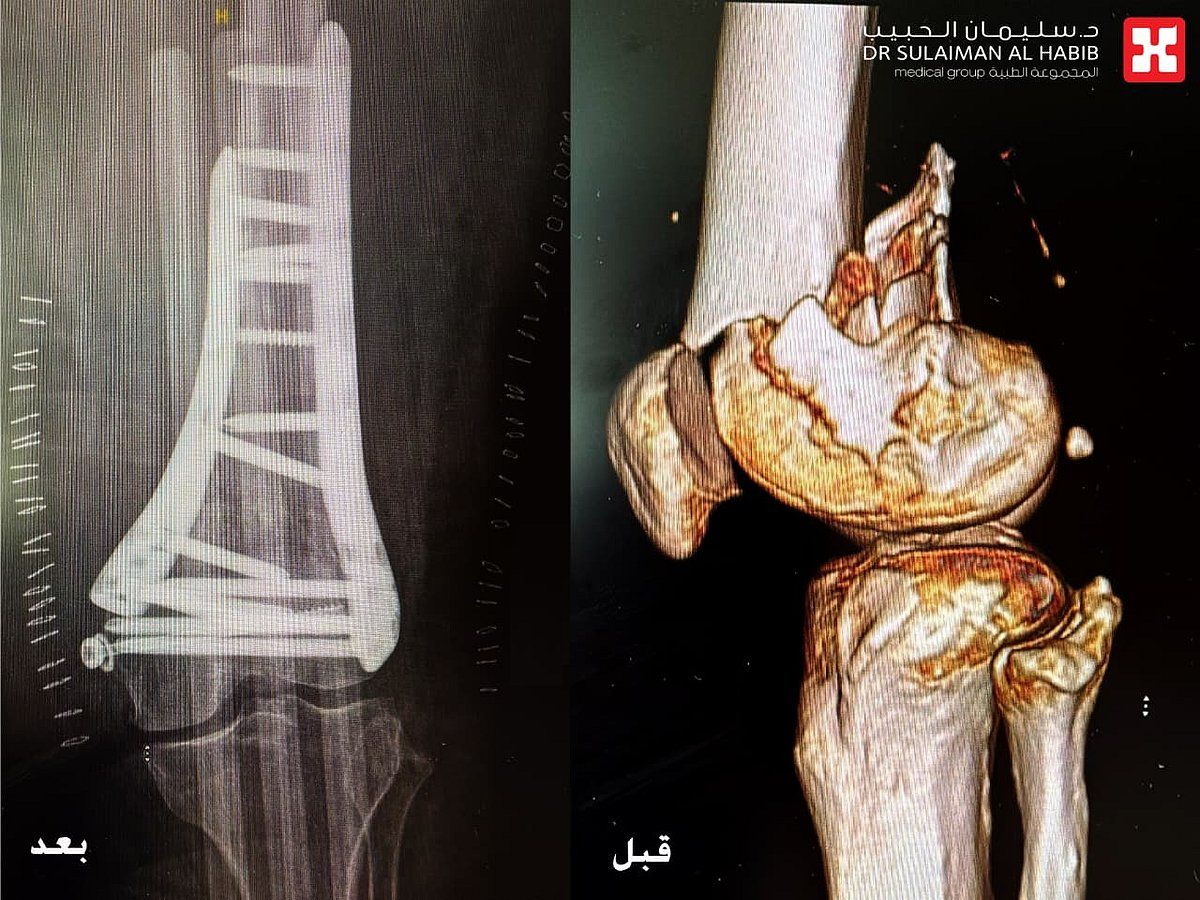

وقال الدكتور العماري أن المراجعة وصلت قسم الطوارىء بعد إصابتها مباشرة، حيث تم تقديم الإسعافات الأولية لها وإعطائها المسكنات اللازمة، ومن ثم إخضاعها لفحوصات طبية شملت التصوير المقطعي (C.T. Scan) والأشعة السينية الرقمية (Digital X-Rays) وتخطيط القلب، بالإضافة إلى التحاليل المخبرية، وقد كشفت النتائج عن وجود كسر كبير من النوع التفتتي المتبدل، والممتد من مفصل الركبة وصولاً للعظم أسفل مفصل الفخذ ، بالإضافة إلى إصابتها بعدد من الأمراض المزمنة مثل السكري وإرتفاع في ضغط الدم.

وأوضح الدكتور العماري أن الخطة العلاجية شملت إجراء فحوصات إضافية مع استشاريي أمراض القلب والباطنية والغدد الصماء، وكذلك الدكتور طارق الزهراني استشاري التخدير، وعقب دراسة كامل معطيات النتائج، تم إتخاذ القرار بالتدخل الجراحي، مشيراً إلى أن العملية استغرقت 3 ساعات متواصلة تحت التخدير النصفي، وتم فيها إصلاح الكسر وتثبيت العظم مع تركيب شرايح وبراغي خاصة للتثبيت، نقلت بعدها المراجعة إلى جناح التنويم.